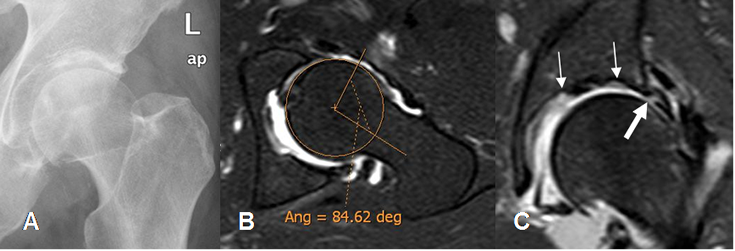

Fig 112. Ruptura del labrum.

A: Rx AP y B: ArtroRM axial oblicua en STIR. Signos de pinzamiento tipo cam, con un ángulo de 84º.

C: ArtroRM coronal en STIR. Defecto del labrum superoexterno, por ruptura. (Flecha gruesa).

Adicionalmente hay irregularidad y lesión del cartílago acetabular. (Flechas delgadas).